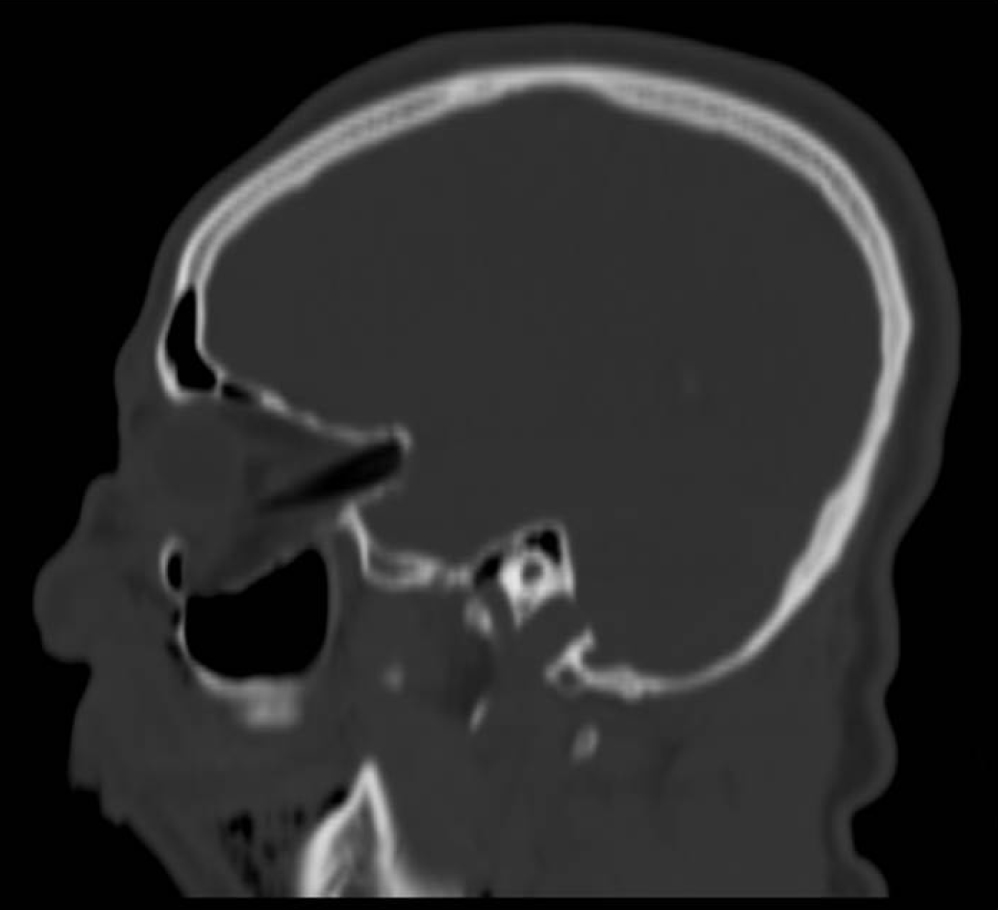

A 25-year-old man was admitted to the emergency room with multi trauma injuries after falling from a second-floor balcony into his neighbor's garden. On arrival, the patient was sedated and placed under artificial respiration. On physical examination, the only external evidence of injury was a 1.5 cm wooden foreign body protruding from the upper lip (Figure 1). Closer examination revealed the foreign body inside the cheek without penetrating the oral cavity. Computed tomography (CT) of the head and face were performed. The images depicted a well formed, radiolucent area with a density similar to that of air in the right orbit. This was later identified as a foreign body penetrating the right orbit in an axial plane from inferior to superior direction. It deflected the globe and penetrated the orbital apex towards the middle cranial fossa to the point of touching but not penetrating the dura mater (Figure 2). A fracture in the floor of the right orbit without the involvement of the lower orbital rim was revealed (Figure 3). Herniation of the inferior Rectus muscle and fat from the orbit into the right maxillary sinus cavity were present (Figure 4). Ocular examination showed no injuries to the globe. The patient received tetanus toxoid and prophylactic intravenous wide spectrum antibiotics. The patient underwent an emergency operation, in the presence of an ophthalmologist and a neurosurgeon. The approach was extra-oral with the aim of exploring and removing the foreign body. The intra-orbital foreign body proved to be a 9 cm bamboo stick (Figure 5). The bamboo stick was meticulously removed. There was no leakage of cerebrospinal fluid (CSF) and no brain tissue was found during exploration examination of the foreign body after its removal. Immediate postoperatively, the patient was transferred to the intensive care. Follow up CT scan demonstrated intact right globe, optic nerve and dura mater. There were no radiolucent findings suggesting that no foreign body remnants were present.

Figure 3: A fracture in the floor of the right orbit. View Figure 3